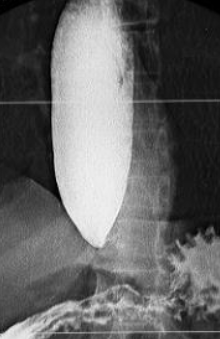

Leiomiom esofagian